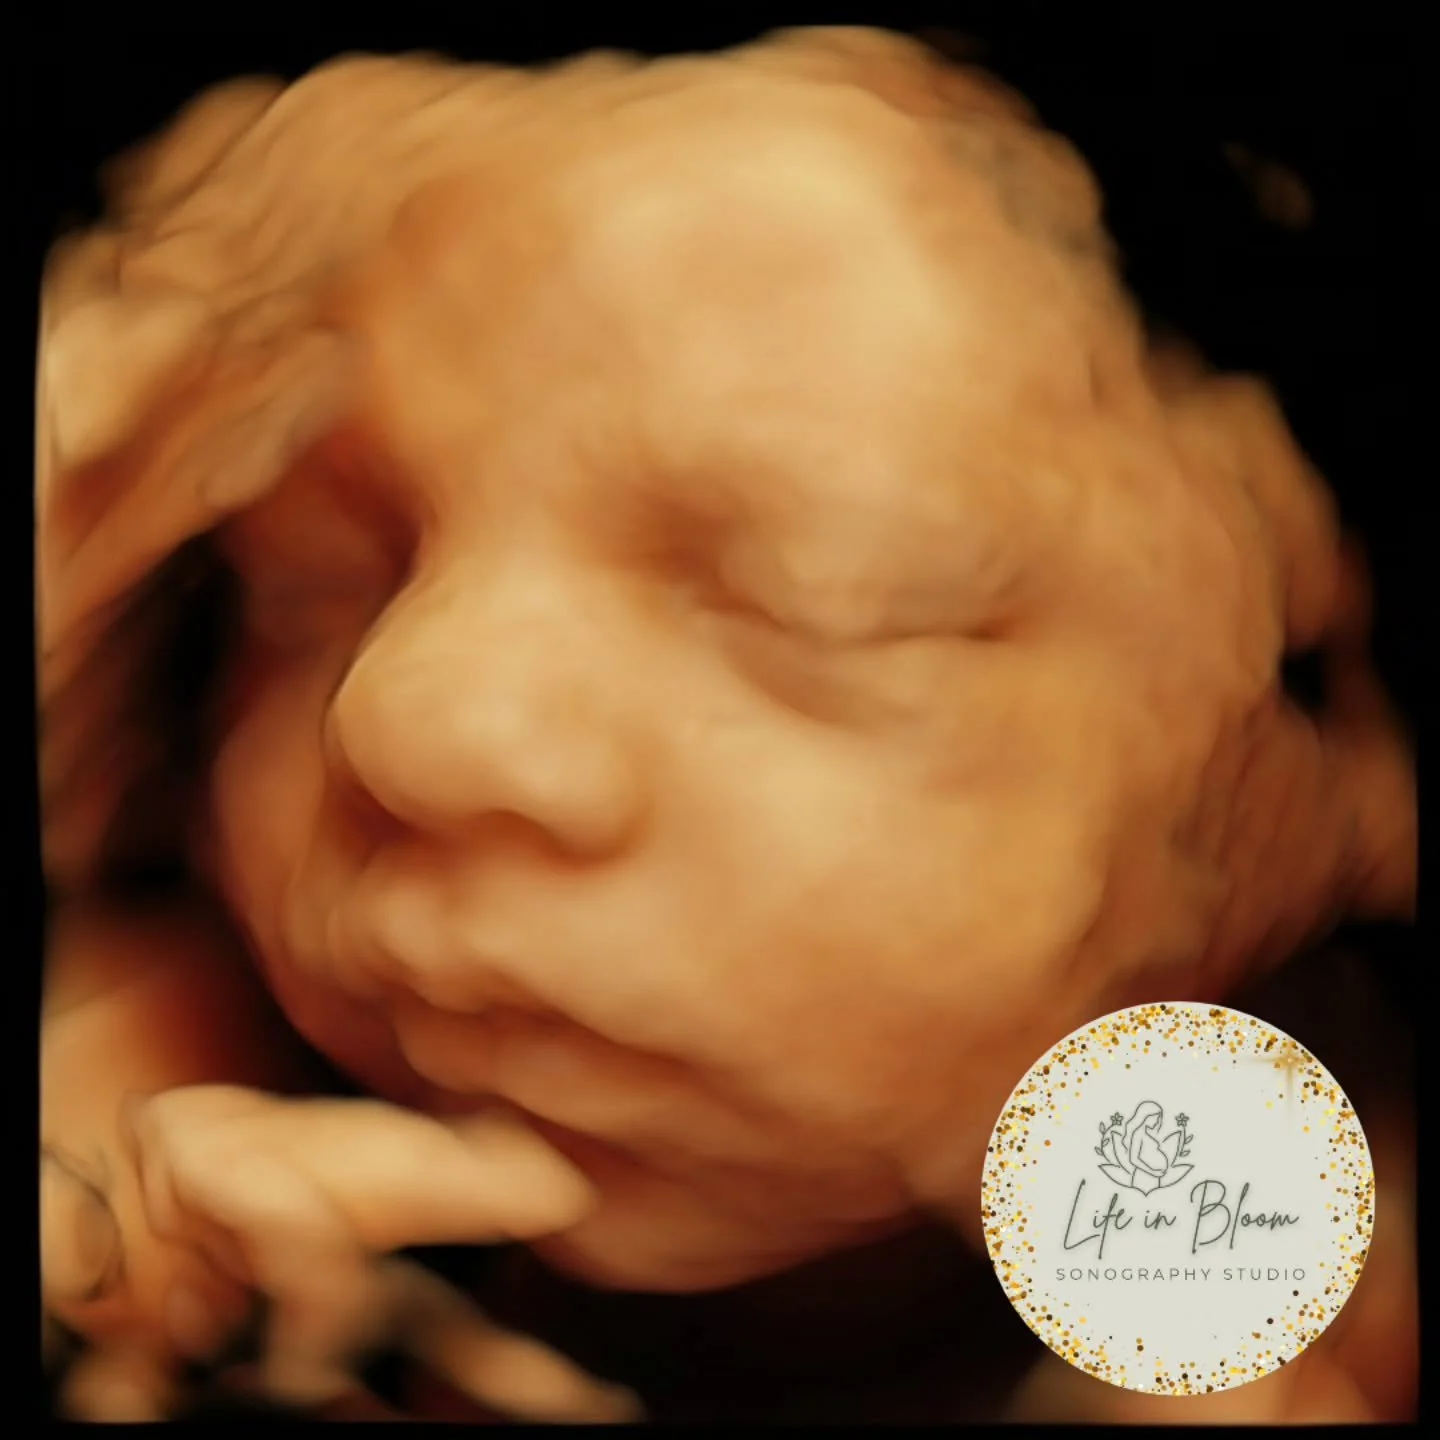

Our state of the art technology allows us to see your baby in a whole different way! With HD Live imaging, we can watch your baby wiggle, smile and yawn all in real time!